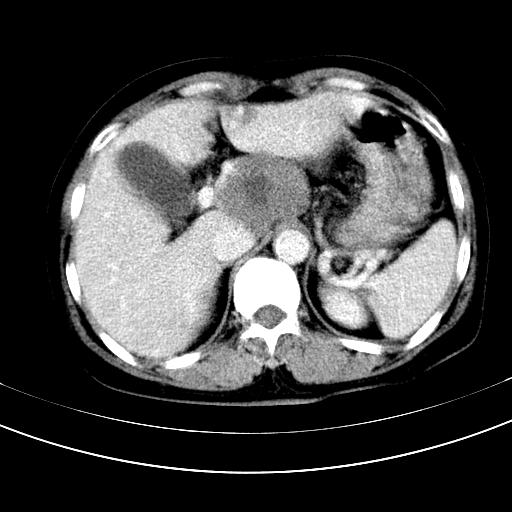

补充强化片

胃内见充盈缺损,建议行胃镜病理检查,如果胃内无占位,则肝内考虑左叶、尾叶为包膜型肝癌,如有则考虑为转移瘤,左侧肾上腺 明显增大,成结节改变,本人考虑转移瘤可能性大。

肾脏前方的是什么,肾上腺吗,

考虑:胃体小弯侧胃癌(或平滑肌瘤恶化或平滑肌肉瘤)伴肝转移,左侧肾上腺转移不除外.

胃癌肝内转移及肾上腺转移。

胃窦部占位伴肝及左肾上腺转移可能大,建议增强扫描。

肝左叶及尾叶低密度灶,增强有渐进性明显强化,考虑血管瘤。胃内“充缺”首先要排除异物(食物),变换体位可鉴别。增强时机抓的不好,还应该有延时像。

谢谢楼主的增强片子,平扫没发现左侧肾上腺的问题很不好意思,可惜片子只有门脉期,所以还只有猜,肝脏的病灶在门脉期部分强化,首先考虑为血管瘤(其他的用一种病不好解释)胃要喝水就好了现在不好说是否有问题,左肾上腺的问题考虑是肿瘤。

做了增强后,可以明确胃是没有肿瘤的,肾上腺也没有肿瘤.肝左叶的病灶首先考虑血管瘤,应该再延迟,肝尾状叶的病灶仍不能排除肝癌的可能性.